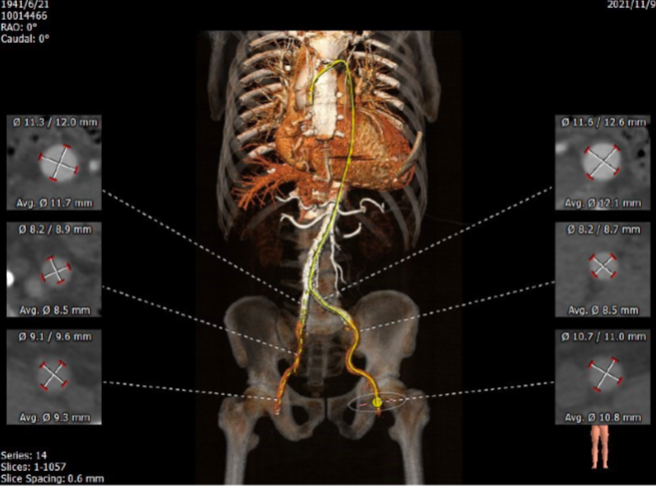

CT评估

入路:左、右股动脉直径均在8mm以上,右股动脉为主入路